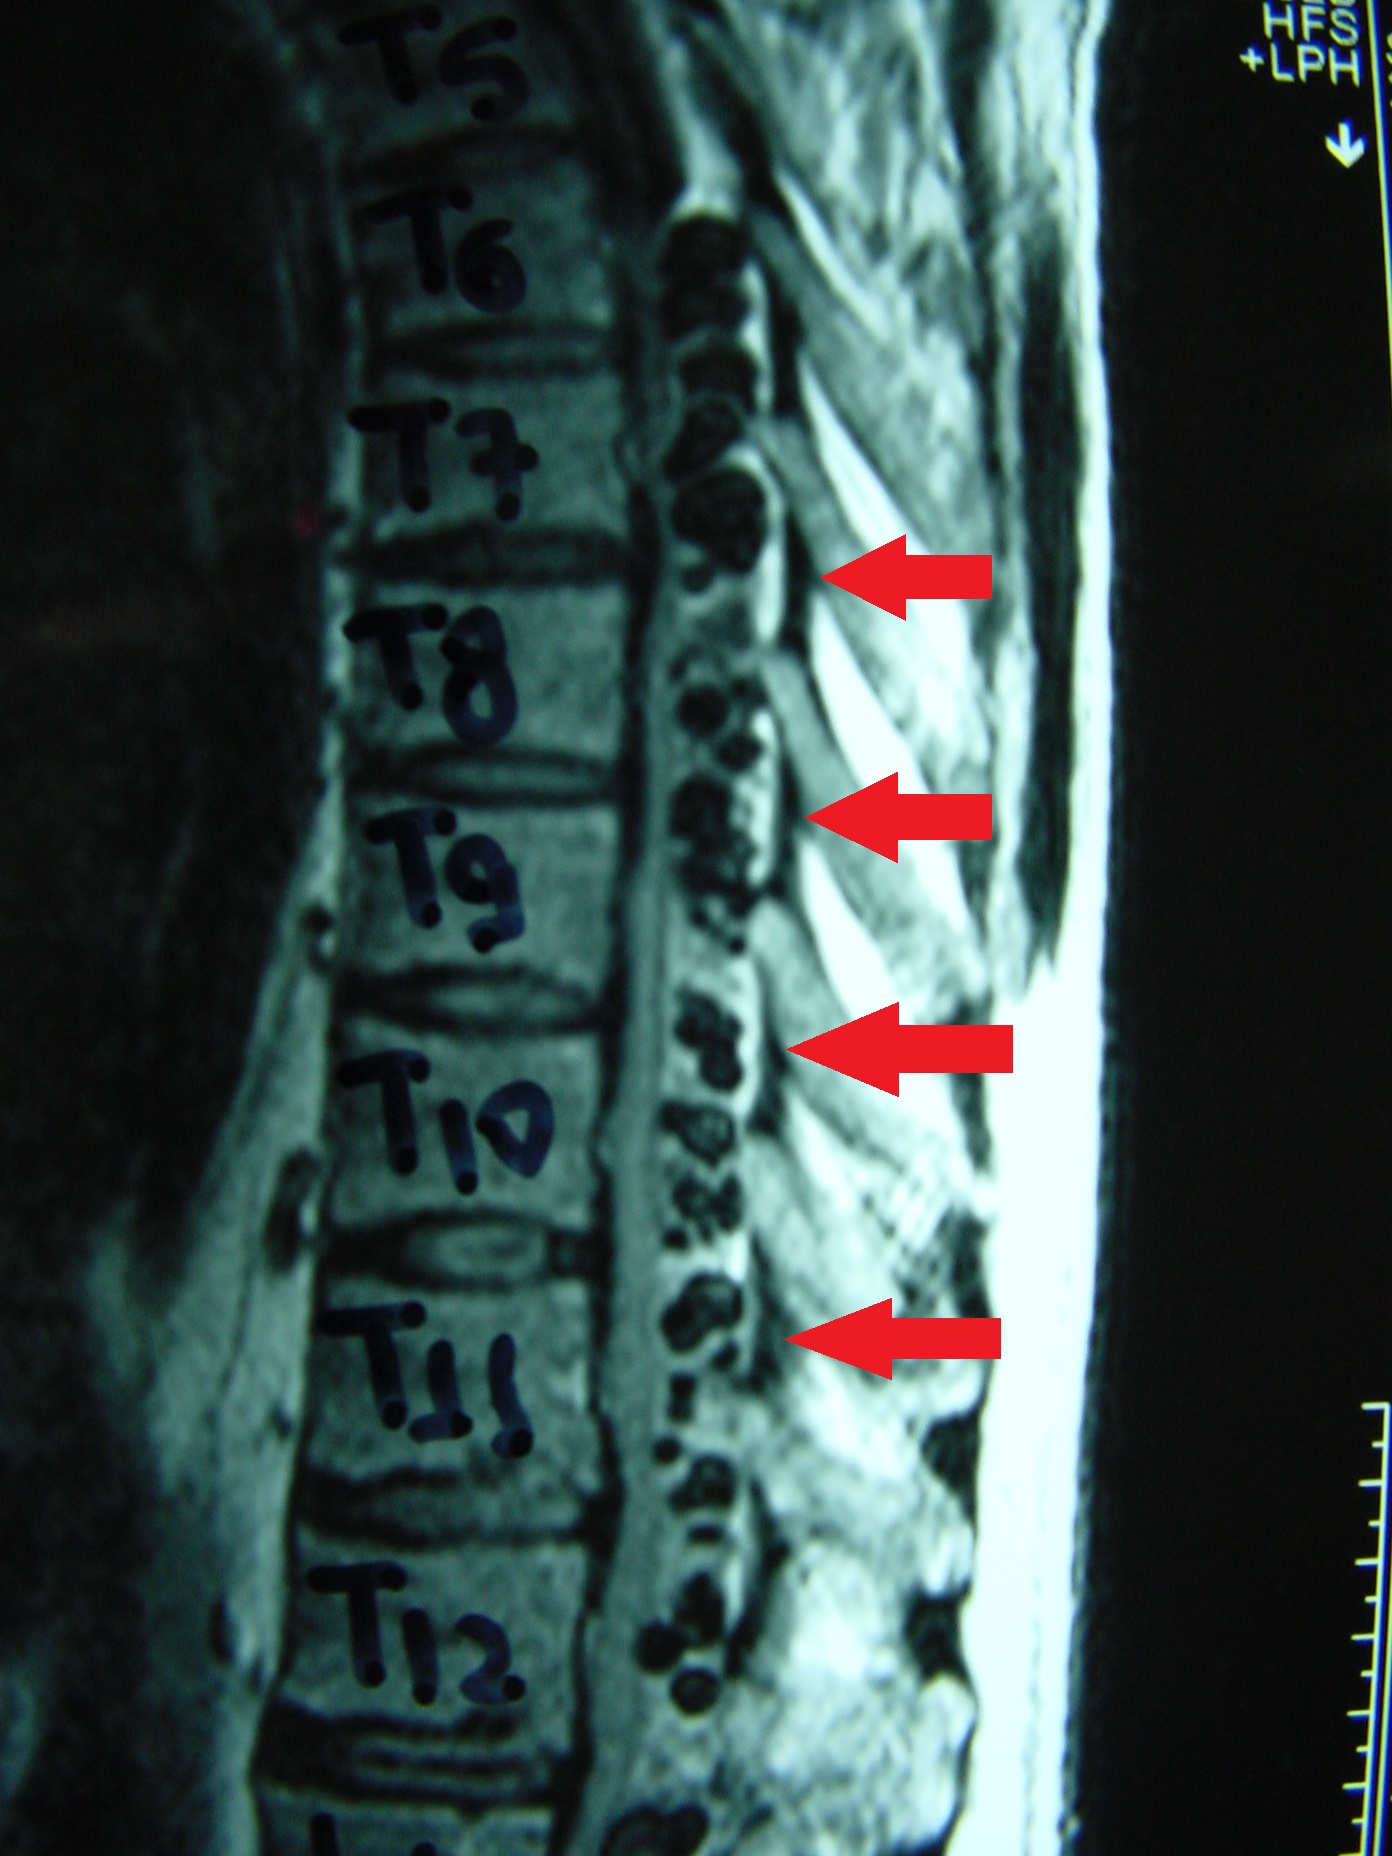

Η μαγνητική τομογραφία μπορεί να βοηθήσει στην απεικόνιση βλαβών στα μαλάκα μόρια και ιδιαίτερα στην προσβολή του νωτιαίου μυελού επί σπονδυλικής εντοπίσεως.

Εικ 3. (α,β) Μαγνητική τομογραφία Σ.Σ. οβελιαία λήψη – ακολουθία Τ1-Τ2, (γ) Εγκάρσια λήψη ακολουθία Τ2

Παρατηρείται η ύπαρξη εχινοκοκκικών κύστεων εντός του σπονδυλικού σωλήνα (βέλη).